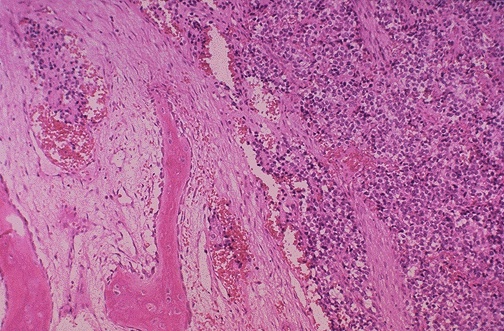

Image 2.4 The lesion is composed of intensely basophilic (blue) staining small round cells seen at the right. The small round cells infiltrate bony trabeculae, with reactive new bone formation seen here at the left. What does this indicate about the biologic behaviour of this lesion? |